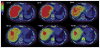

Increased human epidermal growth factor receptor 2 (HER2) expression is a hallmark of aggressive breast cancer. Imaging modalities have the potential to diagnose HER2-positive breast cancer and detect distant metastases. The heterogeneity of HER2 expression between primary and metastatic disease sites limits the value of tumor biopsies. Molecular imaging is a noninvasive tool to assess HER2-positive primary lesions and metastases. Radiolabeled antibodies, antibody fragments, and affibody molecules devise a reliable and quantitative method for detecting HER2-positive cancer using PET. HER2-targeted PET imaging is a valuable clinical tool with respect to both the care and maintenance of patients with breast cancer.